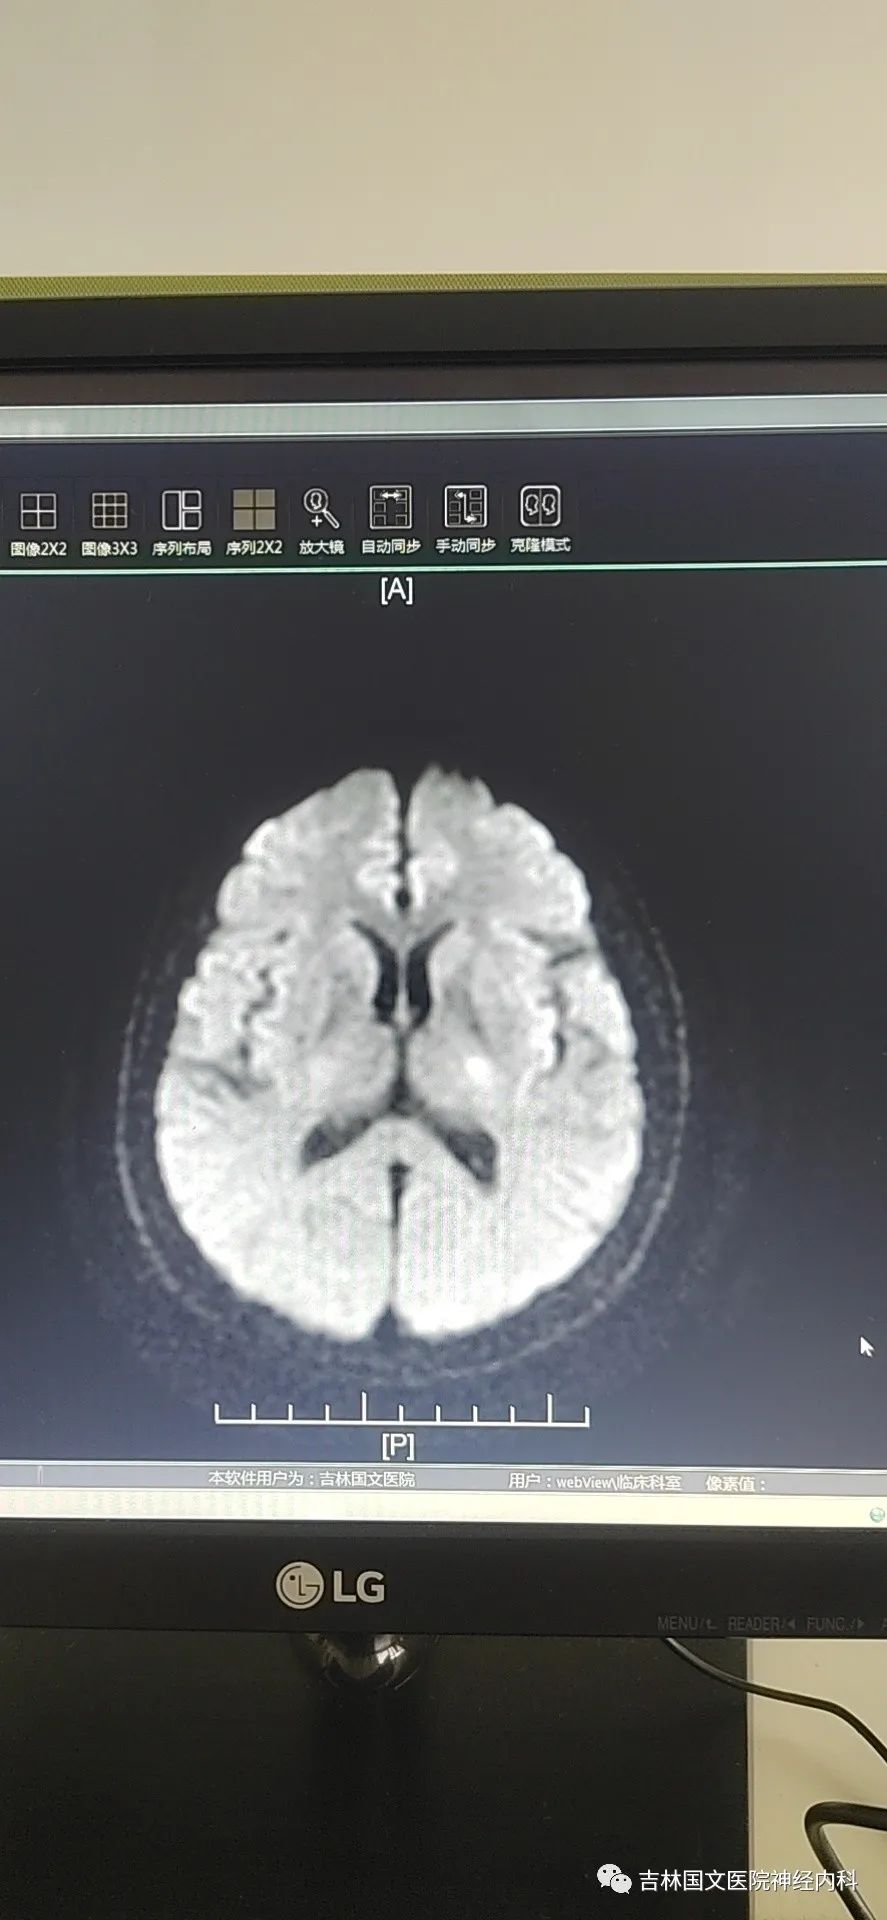

到達(dá)急診后,立即啟動(dòng)“卒中綠色通道”,行頭CT檢查后直入療區(qū)。

入療區(qū)后患者癥狀完全緩解,立即給予心電監(jiān)護(hù),急采血,查體:血壓174/93mmHg,血氧飽和度99%。神志清楚,言語流利,雙側(cè)鼻唇溝對(duì)稱,伸舌居中,四肢肌力5級(jí),肌張力正常,雙側(cè)膝腱反射對(duì)稱存在,雙側(cè)Babinski征(-)。同時(shí)頭部CT結(jié)果回報(bào)未見顱內(nèi)出血。